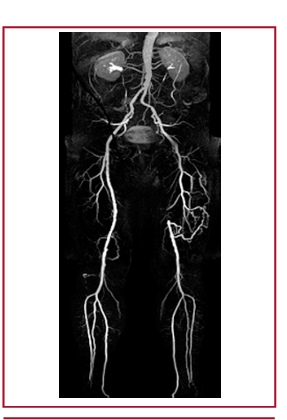

Claudicación intermitente